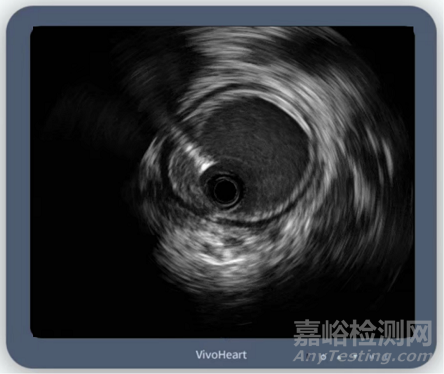

▲頸動(dòng)脈示例,圖片源自北芯生命官微